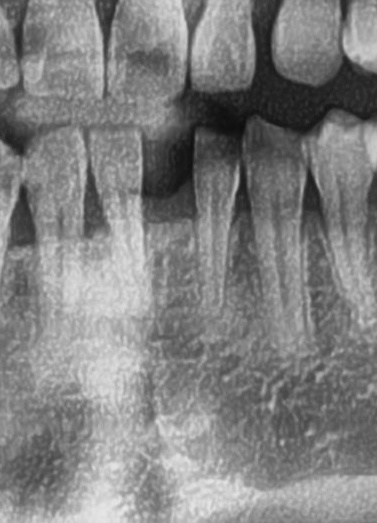

今回の患者様は先天的に欠損している右下1番目、左下1番目にインプラント植立を希望されました。

歯茎から骨の部分までを穴開けパンチの要領で穴を開けていきます。

くりぬいた部分の歯肉を取り除き、次は骨に穴を開けていきます。

ドリルの先端を細い物から徐々に大きい物に変えながら、植立するインプラント体のネジの部分を除いた胴の部分の太さに合わせた大きさの穴を開けていきます。